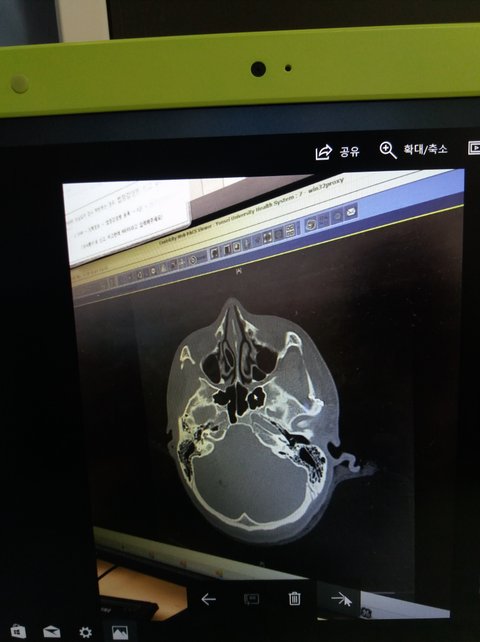

목과 두피가 상처가 있고 가슴이나 배등 찰과상이 있고.. 그리고 응급실에 없는돈에가서

물리치료를 받았지만 완전히낫질않는 마음의상처가... 최근에 공황장애증세(네이버에검색해봤습니다)인거같다고 친구가 그러길래 폭행후부터 가끔 심장이뛰고 너무나 숨이안쉬어지고 팔다리가 잘저립니다... 그때 생각을 다시하면서 글쓰는것도 솔직히 좀 힘듬니다... 먹고살기 힘들어서 신경정신과를 1년간 못가보다가 최근 신경정신과도 가서 여러 약을 처방받아서 먹으며 떨리고 불안한증세를 완화시키고 있습니다 .. 최근 천사같은 변호사님4분의 도움으로 재판을 진행 하고 있습니다..3번의 재판을 저혼자 눈물로 발언권없이 버텨왔고. 4번째 재판이지나고 이번달 10월중순~말경이 5번째 재판입니다... 재판 20대 초반을 송두리째 뺏긴 저에게 20대 중반까지 폭행의 기억으로 앗아가진 말아주세요 하나님 아버지... 그리고 그 때 저 위로해주신 여성분들 제가 항상 늘 건강하시고 복 돼고 잘돼시리라고 격려하고있습니다....... 나타나주시면 정말 제 생에 이만한 큰 원통함이 풀릴일은 다시는 없을겁니다...